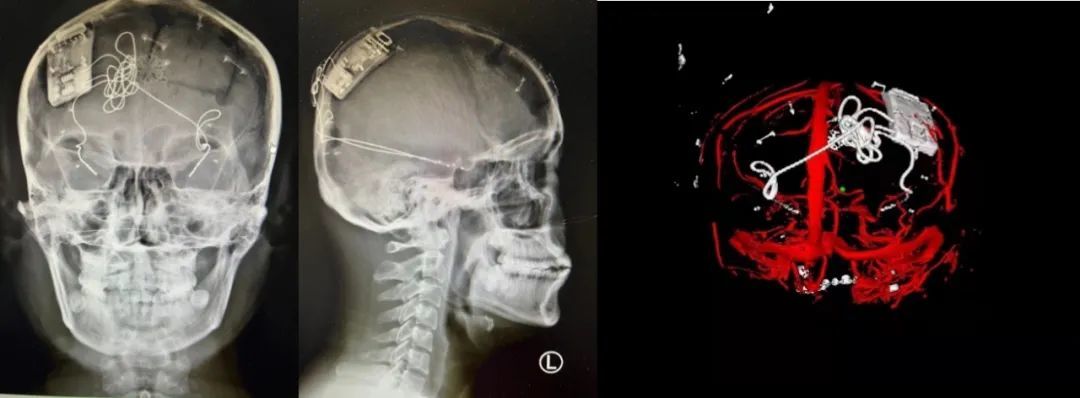

本次手術過程順利,術中刺激器各項指標均工作正常,術后重建顯示電極位置精準,腦電信號清晰?;颊邽槟行?,入院后診斷為雙側顳葉癲癇,此類癲癇為開顱手術的相對禁忌癥,在藥物無法控制的情況下,傳統治療效果欠佳 。

團隊根據術前計劃,在手術機器人輔助下完成雙海馬長軸電極及 IPG 植入,術后重建顯示電極位置精準,腦電信號清晰。術后第二天,患者即下床活動,身體狀況恢復良好。